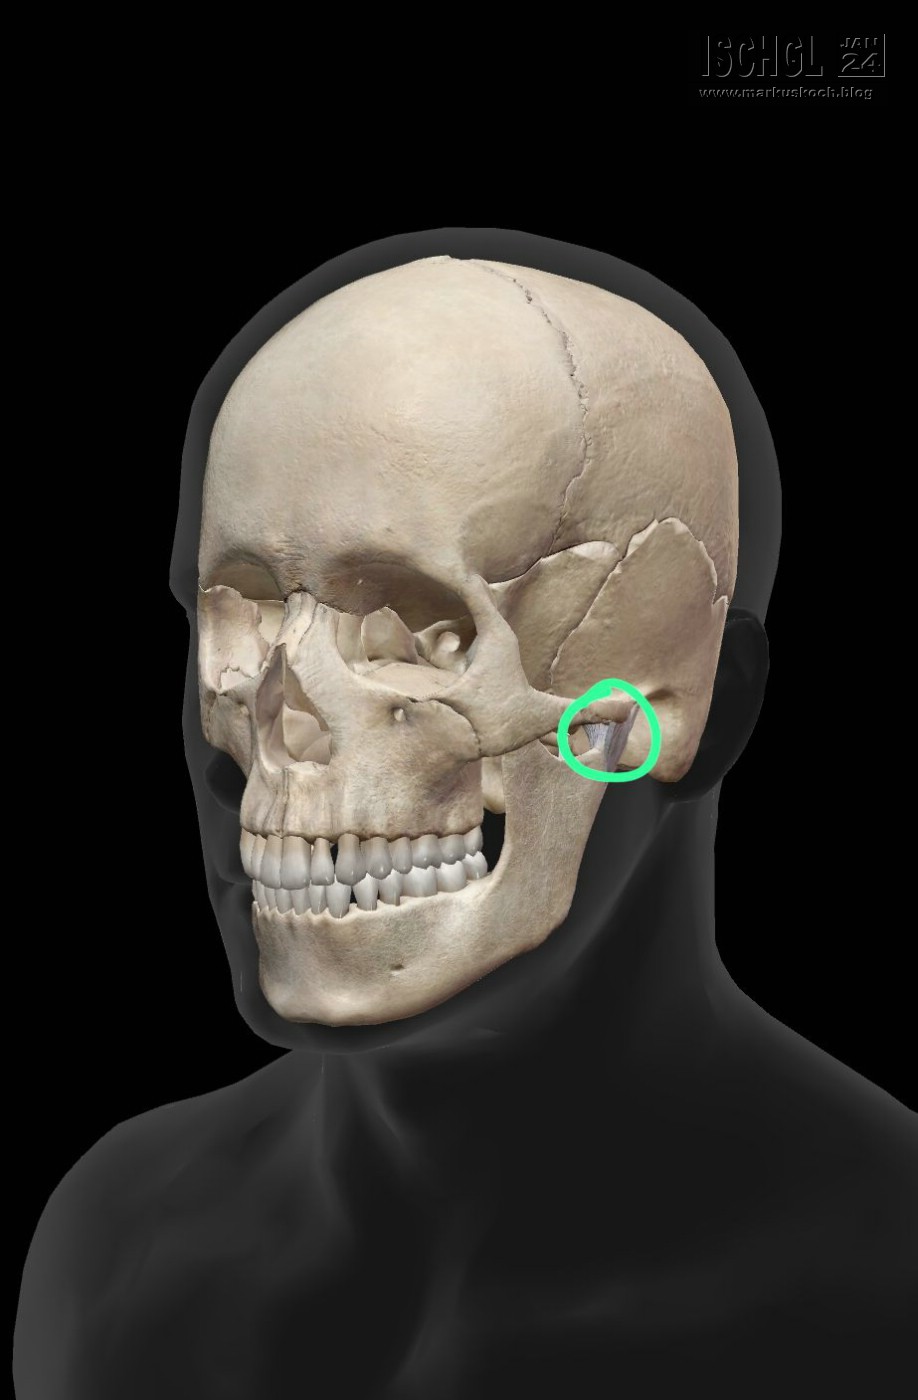

Leider ist Luca auf der Eislauffläche bzw. am nicht präparierten Rand beim Bremsen aufs Kinn gefallen. Anschließend Arzt in Ischgl und weil er nicht so exakt am Kopf röntgen konnte, sollten wir nach Zams ins Krankenhaus. Dort wurde dann genau nachgeschaut und sogar ein CT gemacht. Leider hat sich herausgestellt, dass er sich das Gelenkköpfchen des Unterkiefers gebrochen hat.